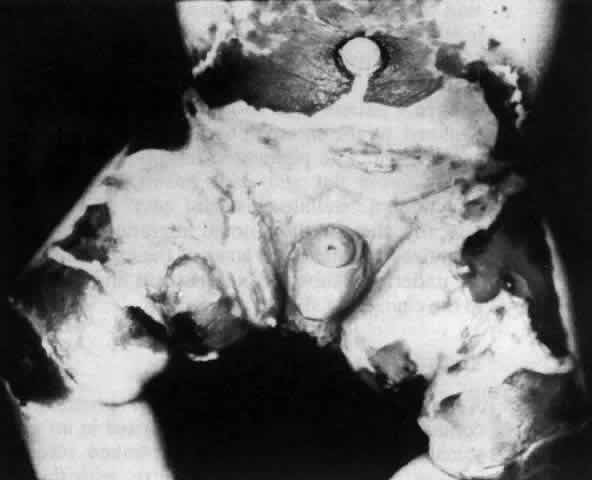

Pemphigus can be differentiated from bullous pemphigoid and from cicatricial pemphigoid on histologic and immunologic bases. Whereas the bullae in pemphigus are intraepidermal, those occurring in bullous pemphigoid and in cicatricial pemphigoid are subepidermal, between epidermis and dermis, or between mucosa and submucosa. Acantholysis is not present in the latter two conditions.5 In bullous pemphigoid and in cicatricial pemphigoid there are tissue-fixed immunoglobulins in the subepidermal basement membrane zone (Fig. 2).11 This is in contrast to the interepidermal fixation of antibodies (Fig. 3) seen in pemphigus (Table 1).

Tissue-fixed immunoglobulins and complement components are present in the epithelial basement membrane zone (BMZ) in patients with cicatricial pemphigoid20,21; indeed, such immunoreactant deposition is the sine qua non for definitive establishment of the diagnosis.20 Circulating antibodies to the basement membrane of conjunctiva are found in all of these patients if ultrasensitive radioimmunoassay techniques are employed,22 and circulating antibodies to conjunctival epithelium have been found (see Table 1).21,23,24 Circulating antinuclear antibodies (ANA) have also been demonstrated in patients with cicatricial pemphigoid.20,25

The diagnosis of OCP is extremely important, given the natural history of the disease, the effectiveness but potential toxicity of therapy, and the potential confusion in differentiation from other causes of chronic cicatrizing conjunctivitis (Table 2). The clinical diagnosis requires immunohistochemical confirmation prior to institution of therapy20; the diagnosis is confirmed by the demonstration of one or more immunoreactants at the epithelial basement membrane zone (see Fig. 2).